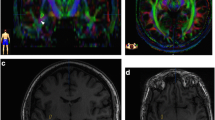

In this work, we also present the virtual dissection of the left hemisphere IFOF of a single subject. Figure 13 displays the whole IFOF with all subcomponents color-coded in the same way as they are depicted in Figs. 14 (superficial component) and 15 (deep component). Figure 14 displays the superficial component as defined by the part of the IFOF directed to the IFG. Figure 15 displays the IFOF without the superficial component.

In this picture all subcomponents color-coded of IFOF are shown with DTI. The superficial layer of IFOF bundle is displayed in red color and the three portions of deep layer, posterior, middle and anterior are colored in green, orange and blue, respectively. a axial view; b sagittal view; c coronal view

DTI reconstruction of the deep layer after removal of the superficial layer. The anterior component is displayed in blue, the middle in orange and the posterior one in green. The DTI results confirm, once again, the course and terminations territories demonstrated in the cadavers dissections. a axial view; b sagittal view; c coronal view

To simplify the description of DTI results, we will assume a postero-anterior course of the IFOF with a posterior origin and an anterior termination. Similarly to what described by Lawes et al. (2008), we found three main apparent origins of the IFOF located in the occipital inferior gyrus, in inferior portion of the occipital middle gyrus and to a minimal extent within the lingual gyrus. Within the occipital inferior gyrus, it is possible to identify two apparently separate stems: one located in the most anterior and lateral part at the border with the inferior temporal gyrus, the other located in a more medial and posterior region at the border with the fusiform gyrus. From these regions the streamlines follow a path that closely resemble the one described in the anatomical dissection both in the paper by Lawes et al. (2008) and in that of Martino et al. (2009). Streamlines converge and pass through the extreme capsule where the whole tract appears to be compacted. The terminations of the streamlines at the frontal lobe closely match the ones previously described in the anatomical dissection, i.e., they reach four distinct areas: the IFG, the lateral OFC, the medial portion of the MFG and the posterior portion of the DLPFC. Based on the anatomical dissection results, we selected the part of IFOF terminating in the IFG to verify its course and location (Fig. 14a–c). This part should correspond to what, based on the anatomical dissection, has been labeled as the superficial portion. We found that it originates from the antero-lateral portion of the occipital inferior gyrus and from the antero-inferior portion of the occipital middle gyrus with a minimal component originating from the lingual gyrus. After passing in the most inferior and lateral portion of the extreme capsule, it turns lateral to terminate in the IFG, closely resembling the anatomical dissection path. Once this superficial component was removed, it was possible to explore the remaining part of the IFOF that should match the deep portion as described in the anatomical dissection (Fig. 15a–c). Notably, immediately after passing through the extreme capsule, where it appears located medially and superiorly to the superficial portion (Fig. 13a–c), it divides into three fan-shaped clusters of streamlines directed, respectively, to the lateral OFC, to the MFG and to the DLPFC (Fig. 15a–c). Following backwards the occipital origin of these three bundles, we found that orbito-frontal part originates mostly from the medial posterior portion of the inferior occipital gyrus at the border with the fusiform gyrus with few streamlines coming from the postero-lateral stem in the inferior occipital gyrus. The other two bundles of streamlines directed to the MFG and to the DLPFC apparently originate almost only from the stem located in the antero-lateral portion of the inferior occipital gyrus at the border with the posterior part of the inferior temporal gyrus.